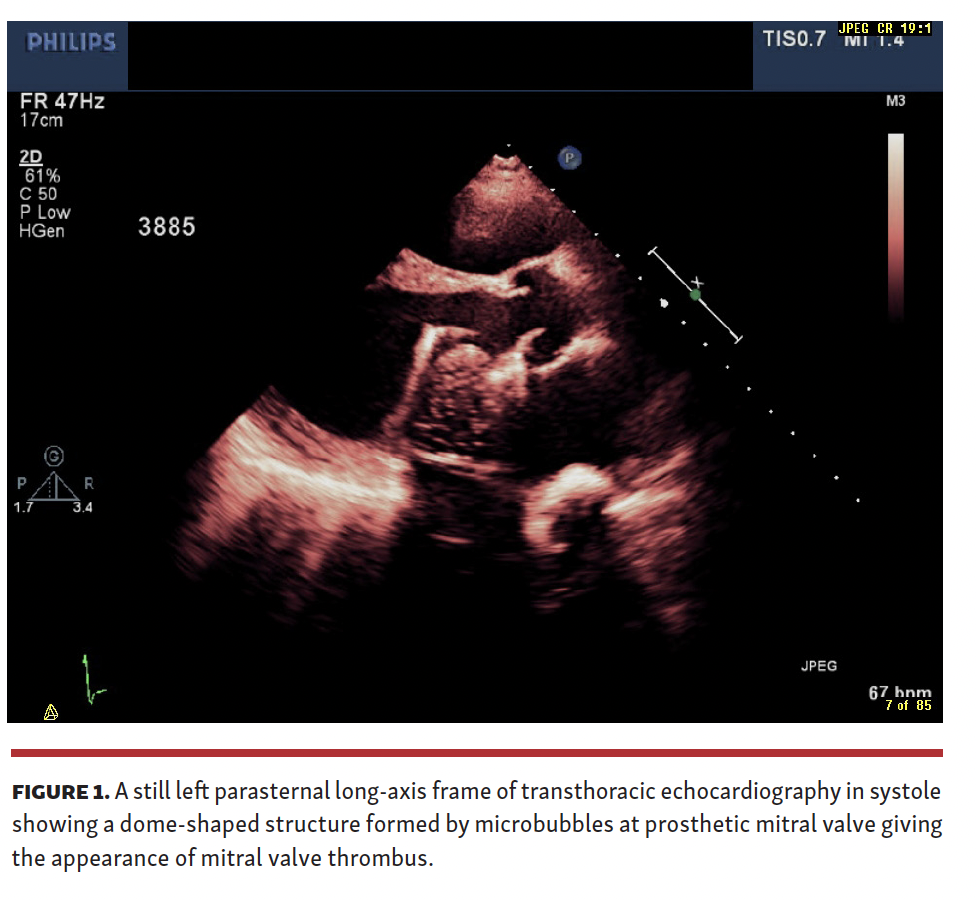

A 36-year-old woman with a history of redo mitral valve replacement (bileaflet mechanical mitral valve prosthesis) in 2002 for prosthetic mitral valve endocarditis presented to the emergency department with a history of recurrent palpitations. Her systemic examination was unremarkable, with a blood pressure of 110/76 mm Hg and oxygen saturation of 100% at room air. A 12-lead electrocardiogram showed atrial flutter with 3:1 atrioventricular conduction. Her complete blood count showed microcytic hypochromic anemia with hemoglobin of 8.8 mg/dL. Thyroid function tests were normal and international normalized ratio was in a therapeutic range of 3.5 on 2 mg of warfarin. She was treated with intravenous amiodarone and heart rate was normalized to sinus rhythm. A transthoracic echocardiogram was performed and falsely indicated a diagnosis of prosthetic mitral valve thrombosis. However, review of the echocardiogram by an experienced echocardiologist revised the diagnosis to microbubbles formation phenomenon with mechanical mitral prosthesis (Figure 1 and Video 1). A transesophageal echocardiogram performed on the same day demonstrated a normal-functioning prosthetic mitral valve and diagnosis of microbubbles formation was confirmed. Frame-by-frame analysis or reducing the frame rate of the recorded echocardiographic loop is vital to demonstrate the growing or dissipation of microbubbles and hence to avoid inadvertent thrombolytic therapy or surgical intervention. The patient remained asymptomatic and persistence of microbubbles formation continued to be observed in a transthoracic echocardiogram at 6-month follow-up.